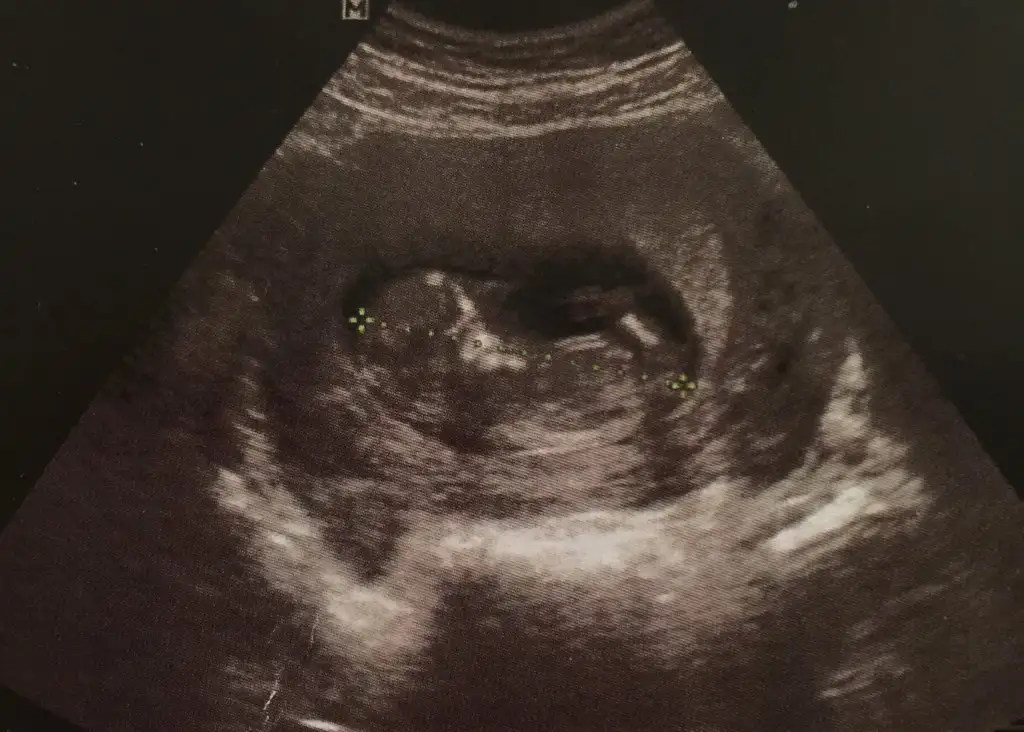

Anaaa :)) bebis erkegim diyoo annesiii doktoe hicmi bisey demedi bariz pipi ortada..Canım, 2 fotosunu daha yorum. Yorum yaparsan çok sevinirim.